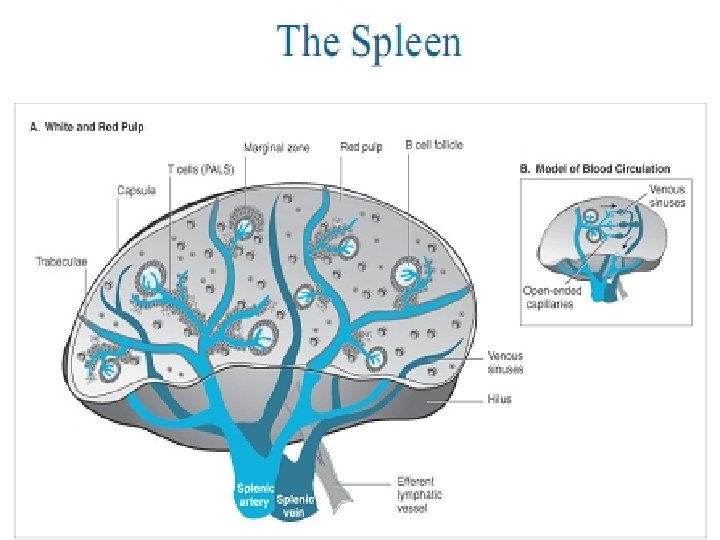

SPLEEN The largest of the lymphoid organs. Splenic pulp is composed of many erythrocytes, leukocytes, and macrophages, as well as a variety of blood vessels, all suspended within a meshwork of mesenchymal reticular cells and fibers. White pulp consists of the lymphoid tissue surrounding each of the many central arteries; it has 2 major components. The sleeves of lymphoid tissue immediately surrounding each central artery are called periarterial lymphatic sheaths (PALS). These contain mainly T lymphocytes and constitute the T-dependent regions of the spleen. Surrounding each PALS, or appended to one side, is the second component, the peripheral white pulp (PWP). PWP contains mainly B lymphocytes and usually includes a typical secondary lymphoid nodule with a germinal center.

Red pulp makes up most of the spleen and also has 2 major components: the red pulp cords and the splenic sinusoids that lie between them. The red pulp (Billroth’s) cords are irregular sheets of reticular connective tissue that branch and anastomose to surround the sinuses. In addition to reticular cells and fibers, the cords contain many cell types, including all the formed elements of blood, dendritic cells, macrophages, plasma cells, and lymphocytes. Splenic sinusoids differ from common capillaries: the lumen is wider and more irregular; there are 2 -3 - m spaces between the lining endothelial cells; and there is a sparse, discontinuous basal lamina that is composed largely of reticular fibers arranged in bands that run roughly perpendicular to the length of the vessel. The marginal zone forms a border between the white and red pulp; it consists of a moatlike arrangement of blood sinuses and loose lymphoid tissue containing few lymphocytes.

Open and closed theories of splenic circulation. Blood in the capillaries reaches the sinusoid lumens by two ways. The closed theory holds that the capillary walls are continuous with the walls of the sinusoids and that the capillaries empty directly into the sinusoid lumens. The open theory holds that the capillaries end abruptly in the red pulp cords and that blood reaches the sinusoid lumens by percolating through the cords and passing through openings in the sinusoid walls. For humans, current evidence favors the open theory. Central arteries and open blood circulation are unique feature for the spleen. Functions: 1. Filtration of blood. 2. Lymphocyte production (lymphopoiesis). 3. Destruction of worn red blood cells 4. Extramedullary hematopoiesis.